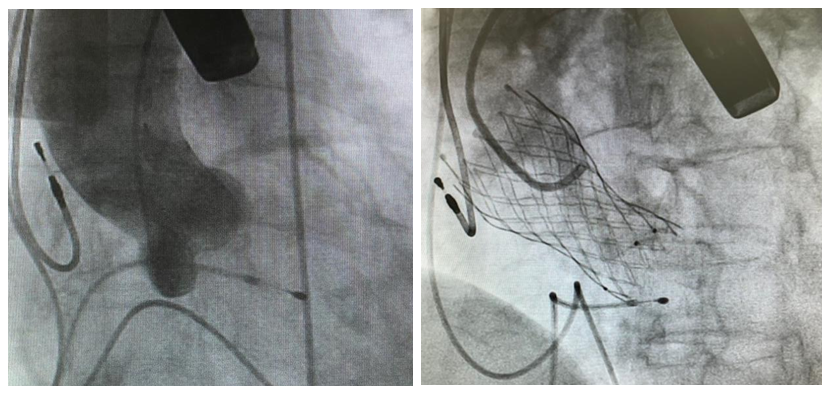

经过术前的精确评估,在多学科团队协同下,姚启恒教授(右)、陈良贵医生(中)、曹高镇医生(左)正在为曾阿姨进行TAVR手术。

术中的精准操作,瓣膜释放定位及膨胀形态良好,研判后决定不行烟囱支架,避免了冠脉支架的植入。

主动脉瓣造影&瓣膜完成释放

姚启恒教授介绍说:“术前评估患者瓣叶明显增厚,左右冠窦部分粘连,法式窦结构不大。术中左冠开口闭塞高风险,团队预先行冠脉保护,主动脉弓降部走行接近直角,过弓可能遇到其他意外困难,很考验术中精准操作。”